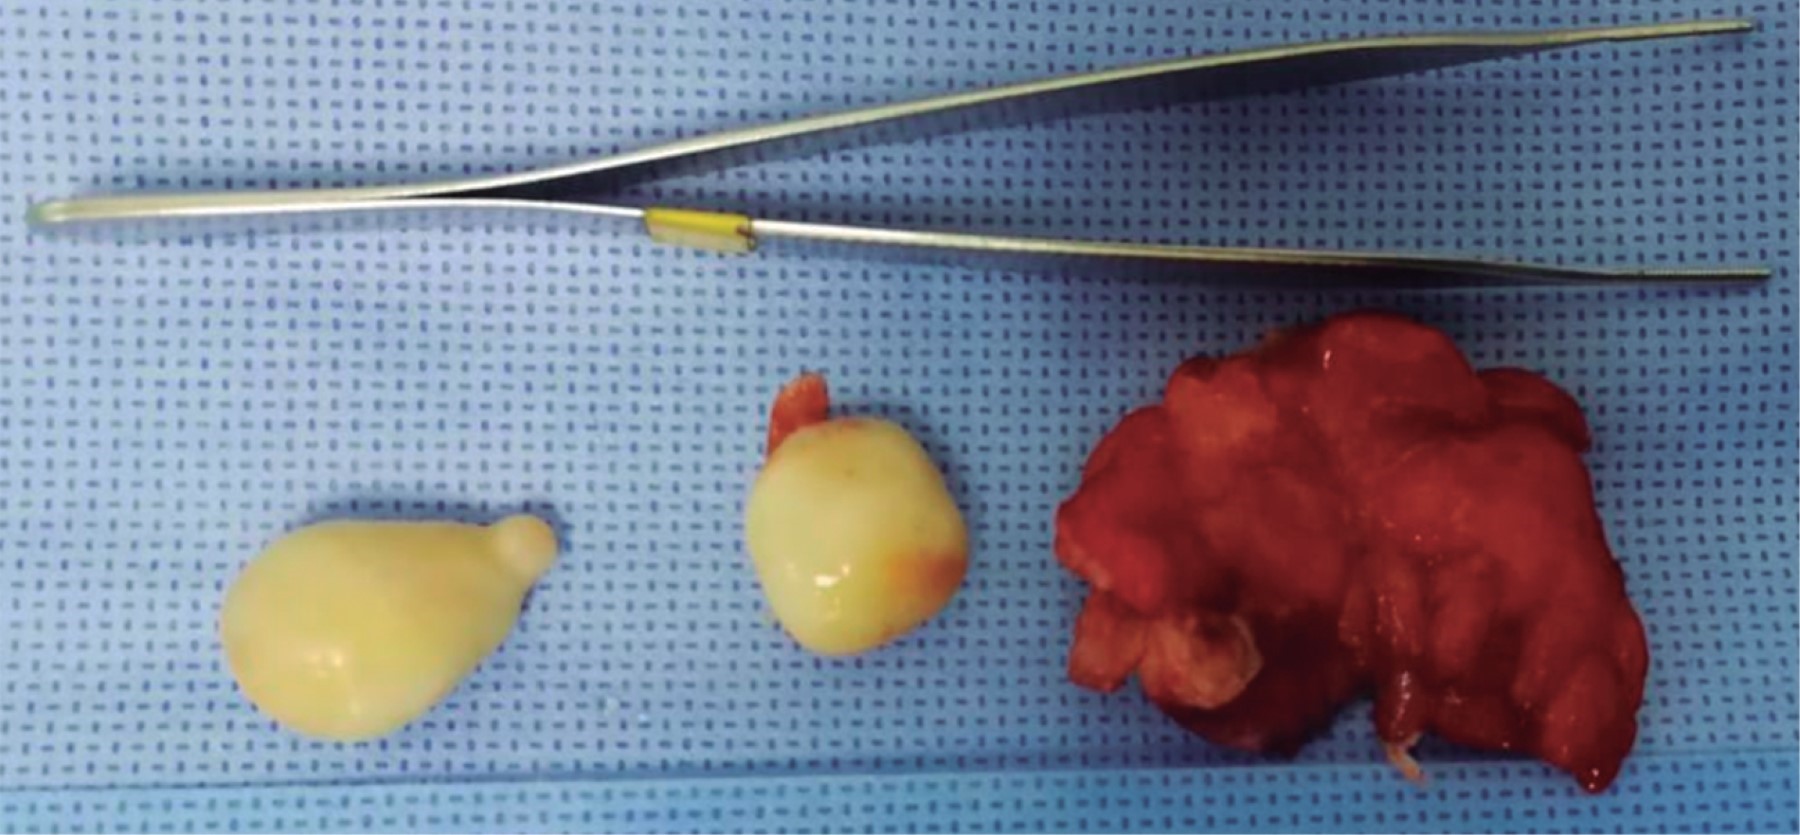

An 81 years-old male presented with a 72-hour abdominal pain evolution, predominantly at the level of the right iliac fossa (RIF), associated with an episode of bacteremia, hyporexia, nausea, vomiting and liquid stools. The abdomen was tender on palpation of the RIF with positive signs of appendix inflammation; hyperactive peristalsis was hard on auscultation and there was evidence of a peritoneal irritation syndrome. His lab tests showed leukocytosis of 11.2 × 103 uL with neutrophilia of 86.9%. An abdominal-pelvic tomography scan with intravenous contrast medium (Figure 1) showed the cecal appendix with data of an acute inflammatory process. Open appendectomy was performed by McBurney incision. Upon entering the abdominal cavity, three free peritoneal bodies were found incidentally, which were sent for histopathological study, together with the resected cecal appendix (Figure 2).

Macroscopic pathological analysis reported three ovoid neoformations of 17 × 15 × 10 mm, 16 × 10 × 10 mm, and 14 × 10 × 10 mm each, with a smooth, yellow, firm surface (Figure 3). When cut they are solid, with a 4-mm whitish gray peripheral thick zone and a yellowish central zone of firm consistency (Figure 4).

Figure 2

Figure 3